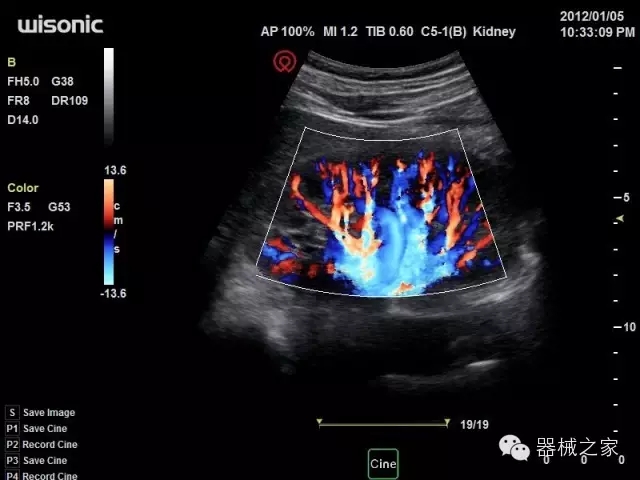

品牌:華聲醫(yī)療(WISONIC)

深圳華聲醫(yī)療技術(shù)有限公司成立于2012年,位于深圳南山西麗湖畔。是一家從事醫(yī)療設(shè)備研發(fā)、制造、營銷的新興高新技術(shù)企業(yè),目前提供生命信息支持、數(shù)字便攜彩超、移動醫(yī)療服務(wù)三個方面的業(yè)務(wù)解決方案。公司核心創(chuàng)始人均為醫(yī)療設(shè)備行業(yè)領(lǐng)軍人物,在醫(yī)療行業(yè)服務(wù)時間平均在10年以上,對行業(yè)和產(chǎn)品積累了深刻的認(rèn)識。公司在創(chuàng)立之初就有著長遠(yuǎn)的戰(zhàn)略目標(biāo)和規(guī)劃,致力于醫(yī)療設(shè)備行業(yè)的細(xì)分市場,貼近客戶所需,為大眾的健康提供更多關(guān)愛。

官方網(wǎng)站:www.wisonic.cn

經(jīng)典產(chǎn)品:四葉草

臨床圖片賞析

產(chǎn)品特點

·全球目前唯一一款配備主機(jī)雙探頭接口,整機(jī)重量(含電池)在5公斤以內(nèi)的便攜式彩超;

·一款互聯(lián)網(wǎng)彩超,只要有手機(jī)信號的地方就可以非常方便地實現(xiàn)遠(yuǎn)程會診和病案調(diào)??;

·鎂鋁合金外殼,堅固可靠耐用;

·獨(dú)有的HoloTM PW 實時3取樣門PW成像技術(shù),精確進(jìn)行血管診斷;

·一鍵優(yōu)化B、Color、PW,Auto Doppler自動識別血管位置、偏轉(zhuǎn)角度等,提高工作效率;

·30°超廣角精細(xì)偏轉(zhuǎn)成像技術(shù),更優(yōu)異的頻譜圖像;

·W+智能搜索引擎,快速尋找圖像;

·SSD、USB3.0保障開機(jī)快,導(dǎo)出圖像更快,減少等待時間;

·WIFI、網(wǎng)口、3G,多重聯(lián)網(wǎng)方式,全天候保障云端備份,不再擔(dān)心圖像丟失;

CFDA注冊證編號

·粵械注準(zhǔn)201522231208